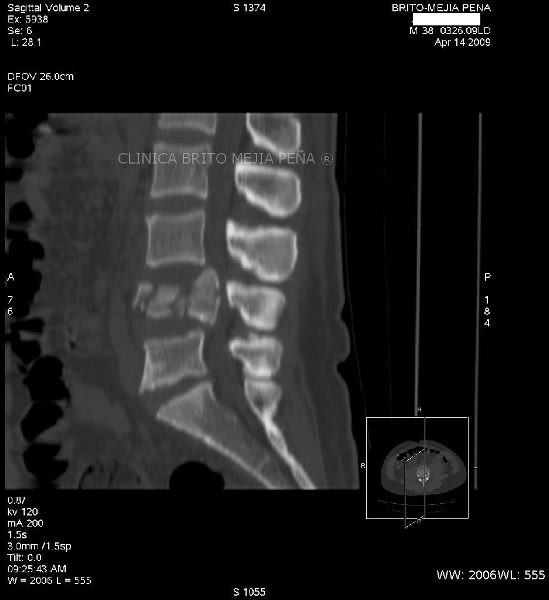

Fractura L4 sagital

Post Image